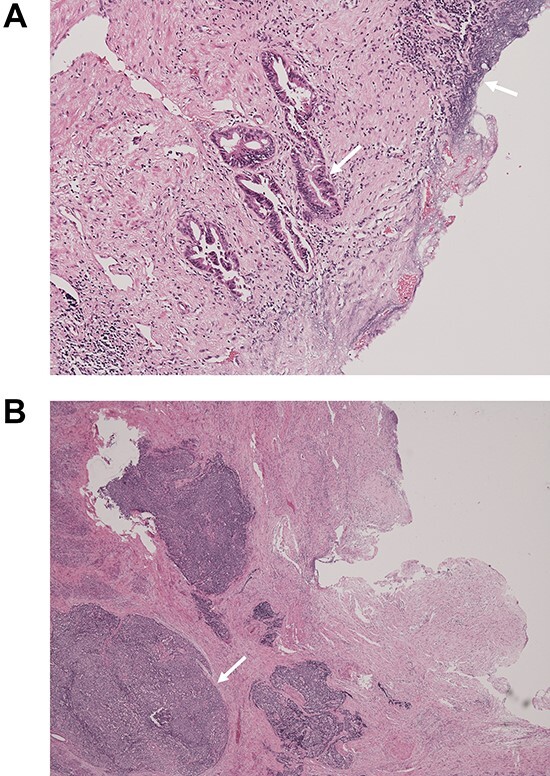

Macroscopically, there was a gray invasive nodular tumor measuring 19 × 18 × 15 mm at the distal CBD (Fig. 4). Histopathological examination showed that the tumor comprised two components; well-differentiated adenocarcinoma of the CBD mucosa (20%) and proliferation of small atypical cells forming follicular nests with invasion around the CBD wall (80%) (Fig. 5a and b). The invasion extended to the pancreas and duodenal muscular layer. Immunohistochemical examination revealed that the solid proliferative lesions of small atypical cells were positive for chromogranin A and synaptophysin (Fig. 6a–c). The Ki-67 index was ~80% (Fig. 6d). No lymph node metastasis was detected. The patient was finally diagnosed with small-cell NEC (pT2N0M0, pStage I B) of the EHBD. R0 resection was achieved pathologically and there was no recurrence for 4 months after surgery.